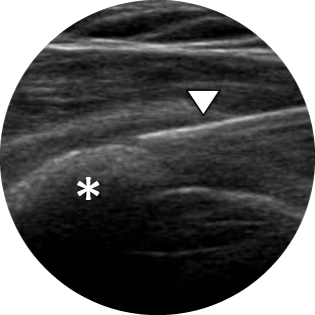

- opravljamo UZ preglede mehkih tkiv

- opravljamo UZ vodeno aspiracijo kalcinatov iz ramena